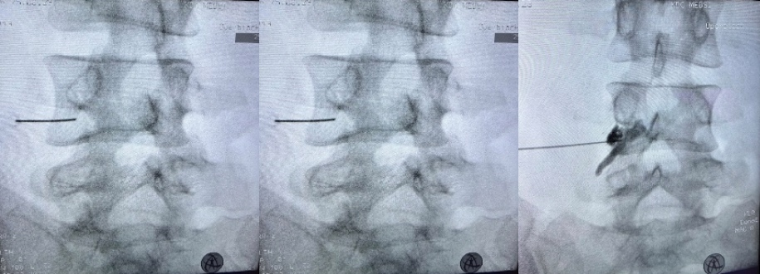

Пациентам под контролем навигации (Рентген или ультразвуковой) проводится ряд инъекций в область эпидурального пространства поясничного отдела позвоночника. Такая процедура позволяет доставить лекарственные средства локально в область конфликта корешка и грыжи межпозвонкового диска, снять воспаление, избавиться от боли и ускорить процессы резобрции грыжи.

Рис. Проведение интервенционного лечения (трансфораминальной эпидуральной блокады на поясничном уровне). Блокада проводится с введением контрастного вещества для определения попадания лекарства в эпидуральное пространство.